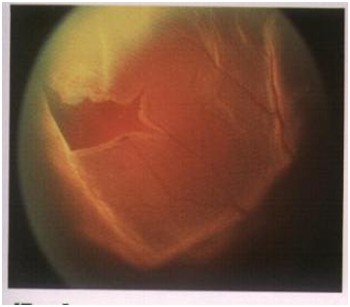

眼底疾病诊治依托北京少妇色情 著名眼底病专家,不定期进行门诊、手术,拥有一批经验丰富、技术过硬的核心团队。引进先进的蔡司眼底造影系统、德国蔡司最新型号Lumeral T手术显微镜、美国Alcon Accurus 2500转高速玻切机、德国蔡司第四代CIRRUS OCT光学相干断层扫描仪等大型检查及治疗设备,应用现代高科技手段和专家团队技术力量,提供眼底全套检查项目,重点开展玻璃体、视网膜疾病手术及激光治疗,诊疗项目涉及玻璃体切除治疗玻璃体积血、简单或复杂性视网膜脱离、严重眼外伤、糖尿病视网膜病变、晶体异常、黄斑病变、视网膜下新生血管膜、化脓性眼内炎、视网膜肿瘤等多种复杂疑难眼底疾病,其中在糖尿病视网膜病变复杂性视网膜脱离、黄斑病变、眼外伤的诊断及手术等疑难眼底疾病方面有独到的建树。